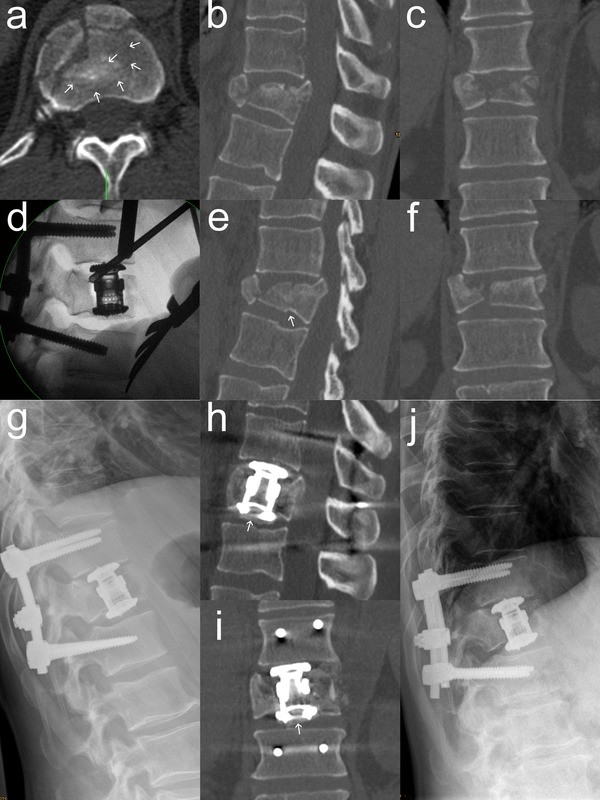

VBRD subsidence was observed in five patients (Table 4). In three of these patients, the VBRD subsided through the inferior endplate of the fractured vertebra and into the adjacent intervertebral disc (Figs. 2, 3). In the other two patients, the VBRD subsided into the cancellous bone until the inferior endplate was reached (Fig. 4). VBDR subsidence through the inferior endplate was already apparent intraoperatively (one case) or on first radiograph after postoperative mobilization (two cases), whereas VBDR subsidence into the cancellous bone occurred later but became evident on follow-up radiographs within 3 months post surgery. When comparing patients with and without VBRD subsidence after monosegmental ACR, however, differences in monosegmental (4.0 ± 2.6° vs. 2.2 ± 2.7°, P = 0.22) and bisegmental (5.8 ± 3.0° vs. 4.9 ± 4.0°, P = 0.67) loss of correction did not reach significance.

Second illustrative case of VBDR subsidence through the inferior endplate after monosegmental ACR. Multiplanar CT reconstructions in the axial (a), median sagittal (b), paramedian sagittal (e) and coronal (c, f) plane showing a complete burst fracture of T12. The fracture may be misinterpreted as a burst-split fracture when analyzing the standard median sagittal and coronal reconstructions only. However, the axial CT reconstruction at the level of the inferior endplate (a) as well as the paramedian sagittal reconstruction (e) clearly depict multiple additional subtle fracture lines at the inferior endplate (indicated by white arrows). Intraoperative lateral radiograph (d) already showing minimal VBRD subsidence after positioning onto the “free floating” central inferior endplate fragment created by the presence of multiple fracture lines. Postoperative lateral radiographs and CT images at 1 week (g–i) and 14 months (j) demonstrating VBDR subsidence through the inferior endplate and into the adjacent intervertebral disc. The central inferior endplate fragment below the VBDR is indicated by white arrows (h, i)